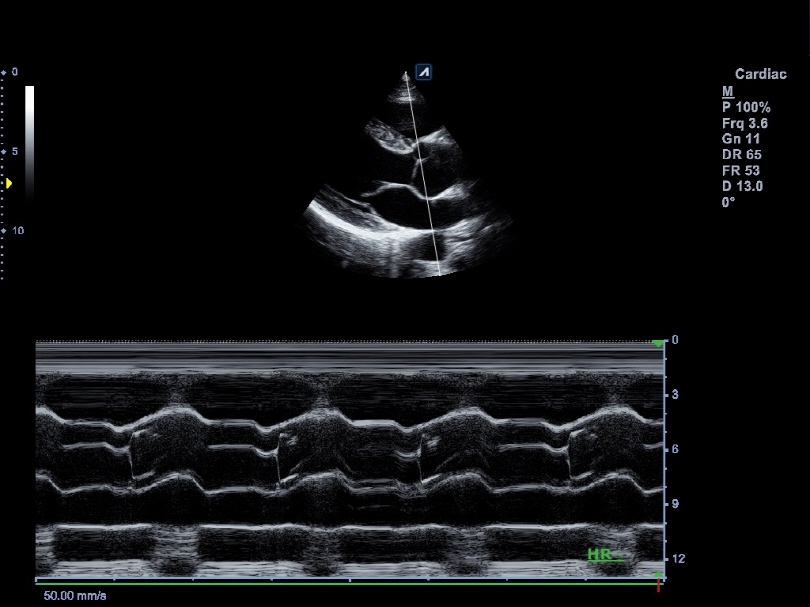

P1-5CT

Single crystal phased array transducer (1-5MHz)

Application:

Abdomen, Cardiac, EM, TCD

SP3-8T

Phased array transducer (3-8MHz)

Application:

Abdomen, Cardiac, EM, Pediatric

CW5.0

Pencil type transducer (5.0MHz)

Application:

Cardiac

CW2.0

Pencil type transducer (2.0MHz)

Application:

Cardiac